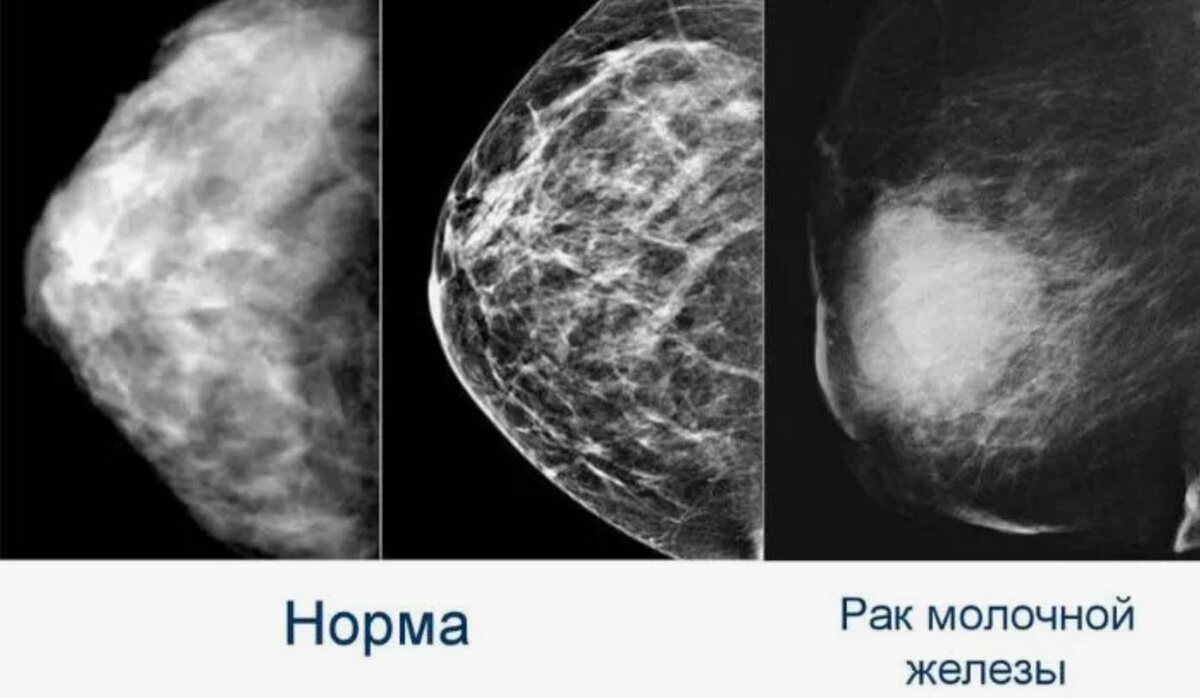

Миф 3: Только маммография помогает в диагностике рака молочной железы

Маммография — это важный метод диагностики, но есть и другие способы, которые могут быть эффективны, особенно в случае молочных желез с плотной тканью, где маммография может не дать точных результатов.

• Помимо маммографии, есть методы, такие как УЗИ молочных желез или МРТ, которые могут быть использованы для более точной диагностики. Эти методы помогают выявить опухоли, которые могут быть не видны на маммографии, и предоставляют больше информации для точной диагностики.